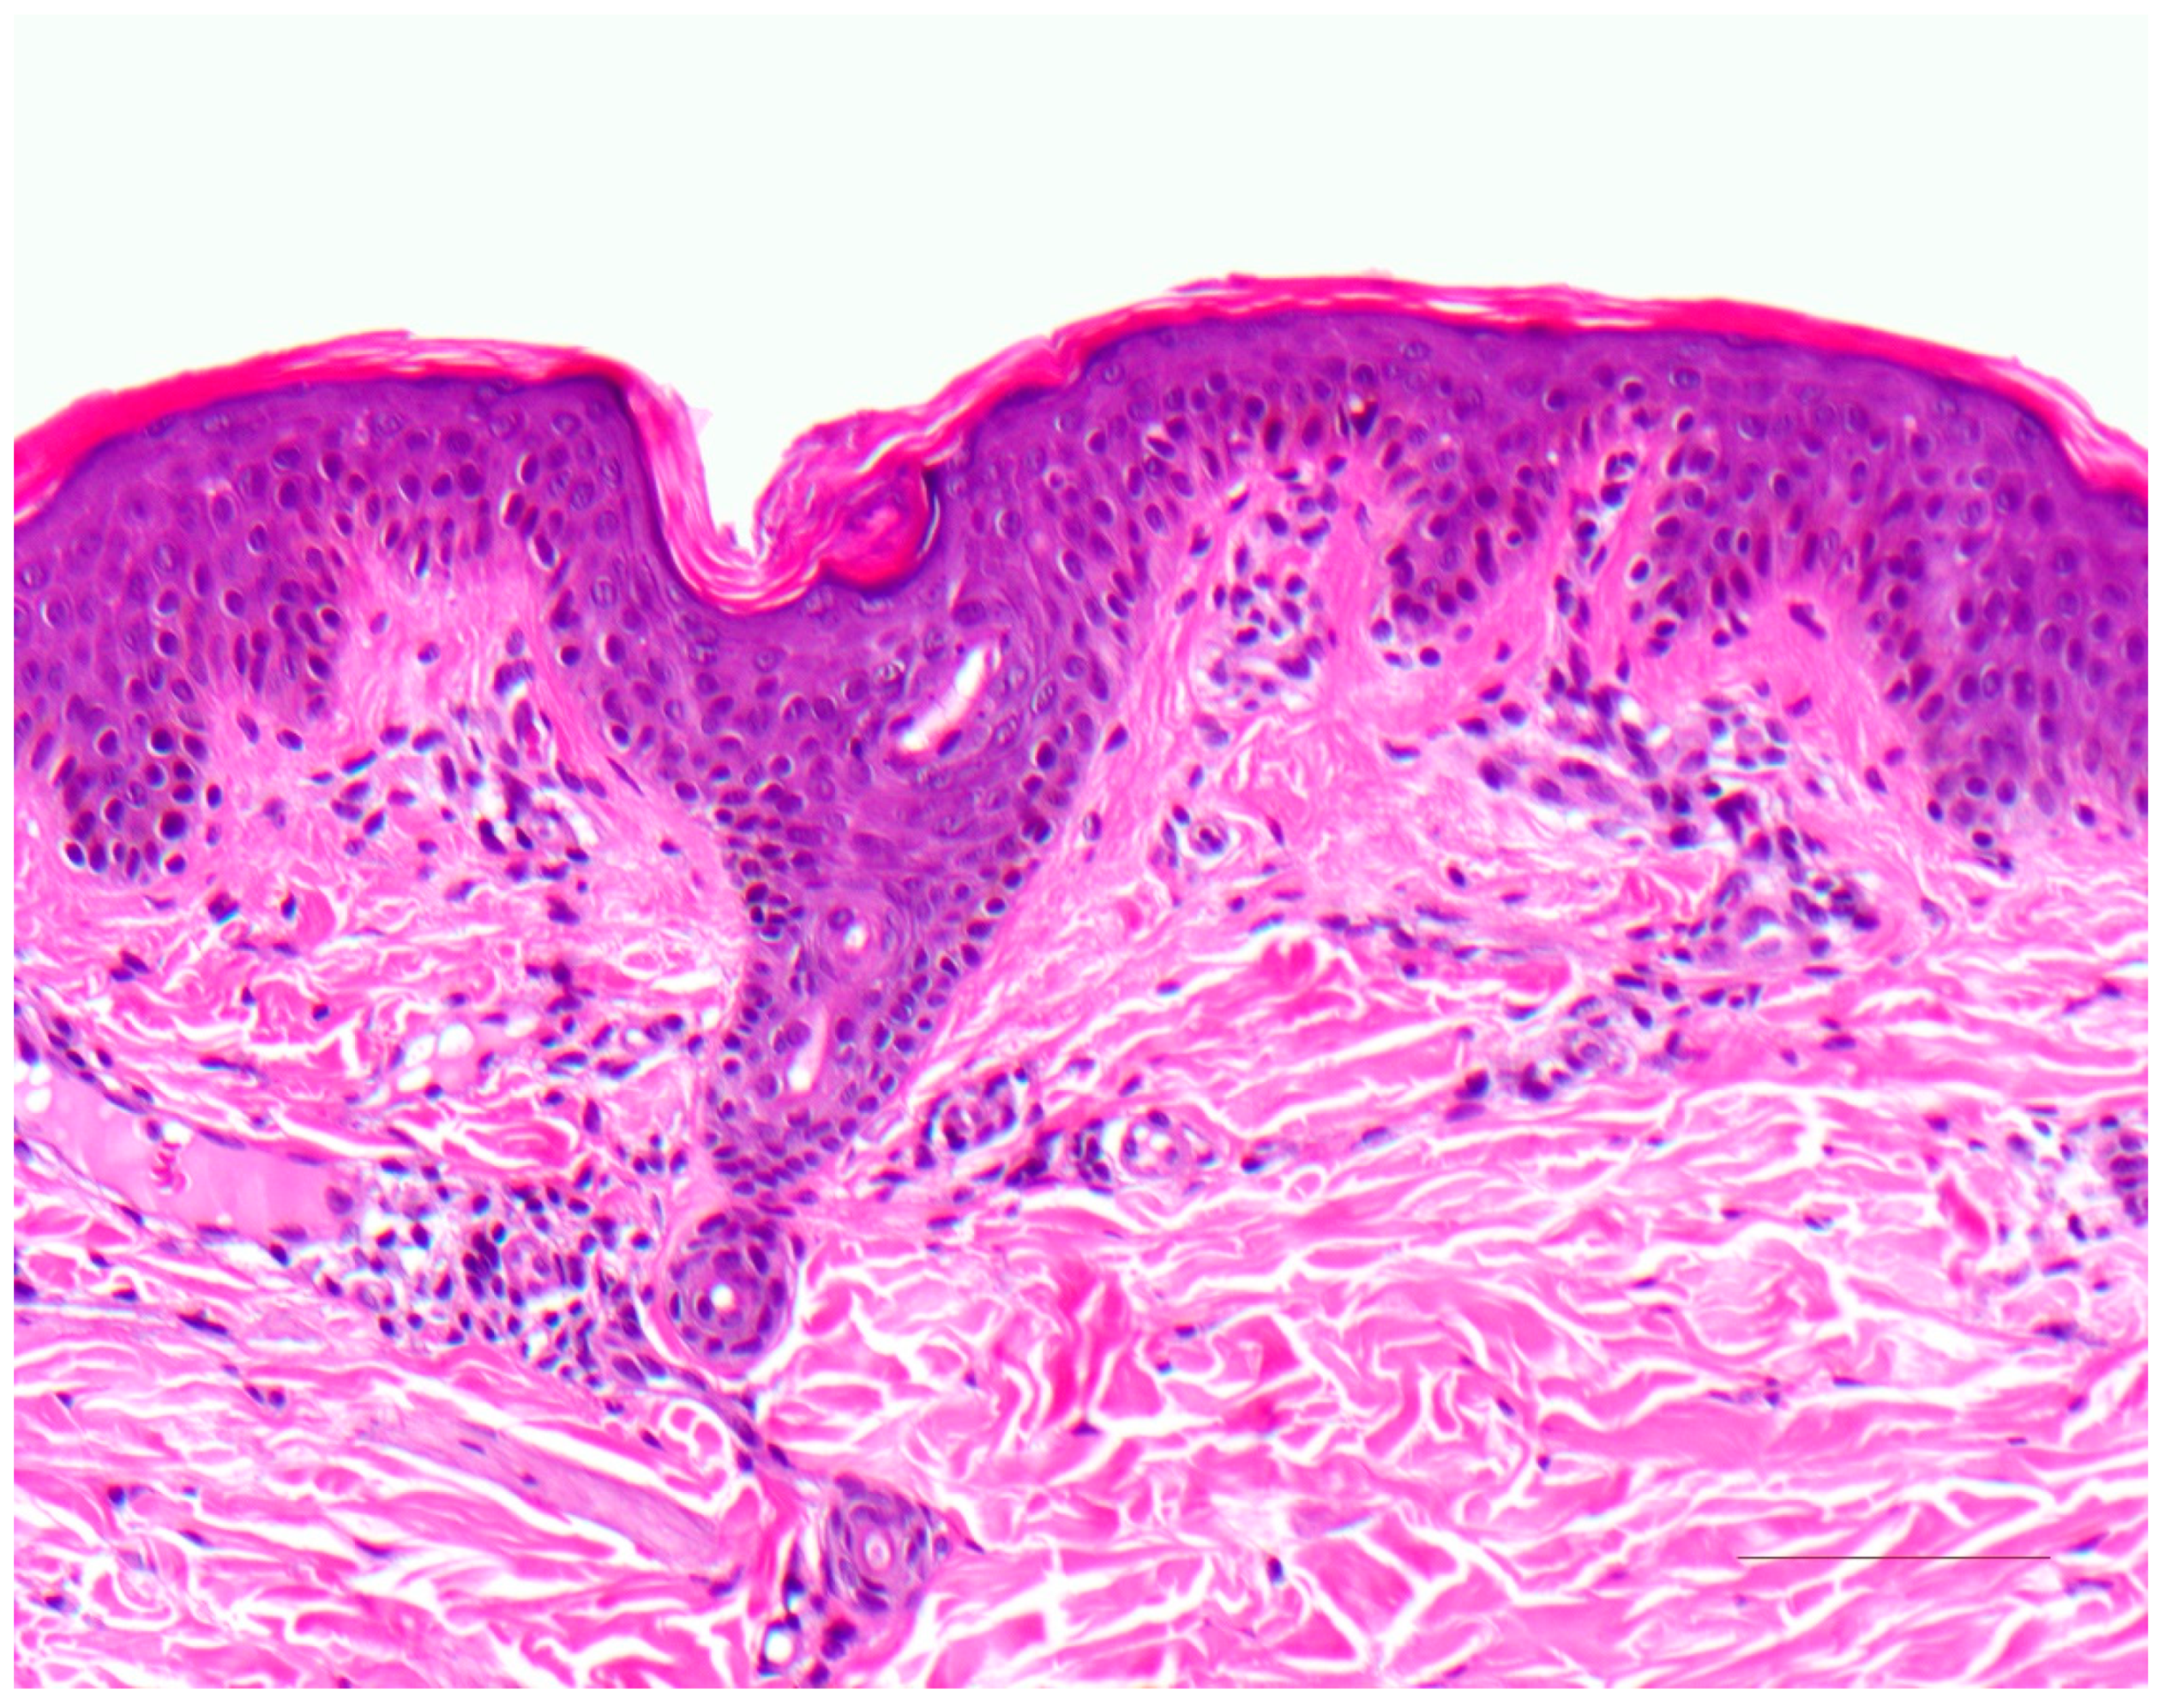

3. Ichthyosis Vulgaris

3.1. Histology